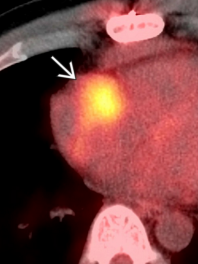

Metastase myocardique melanome progressif

Metastase myocardique melanome progressif